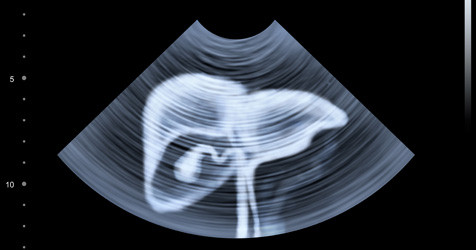

featured image of blog

• Ultrasound: Used to check for an enlarged liver or changes in its shape or texture.